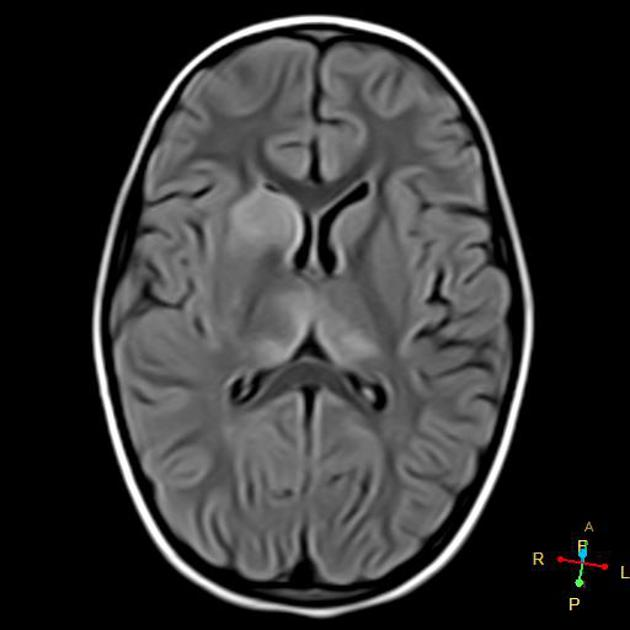

3/ T2-Weighted MRI β Edema & Pathology Detection

π₯οΈ Appearance:

β CSF = Bright

β Edema = Bright

β Gray matter = Bright, White matter = Dark

π Key Uses in Neurosurgery:

β Detects vasogenic & cytotoxic edema (brain tumors, strokes, infections)

β White matter demyelination (MS, PML, leukodystrophies)

β Cystic & necrotic tumor components

π¨ Best for detecting pathological changes!

image: radiopaedia.org